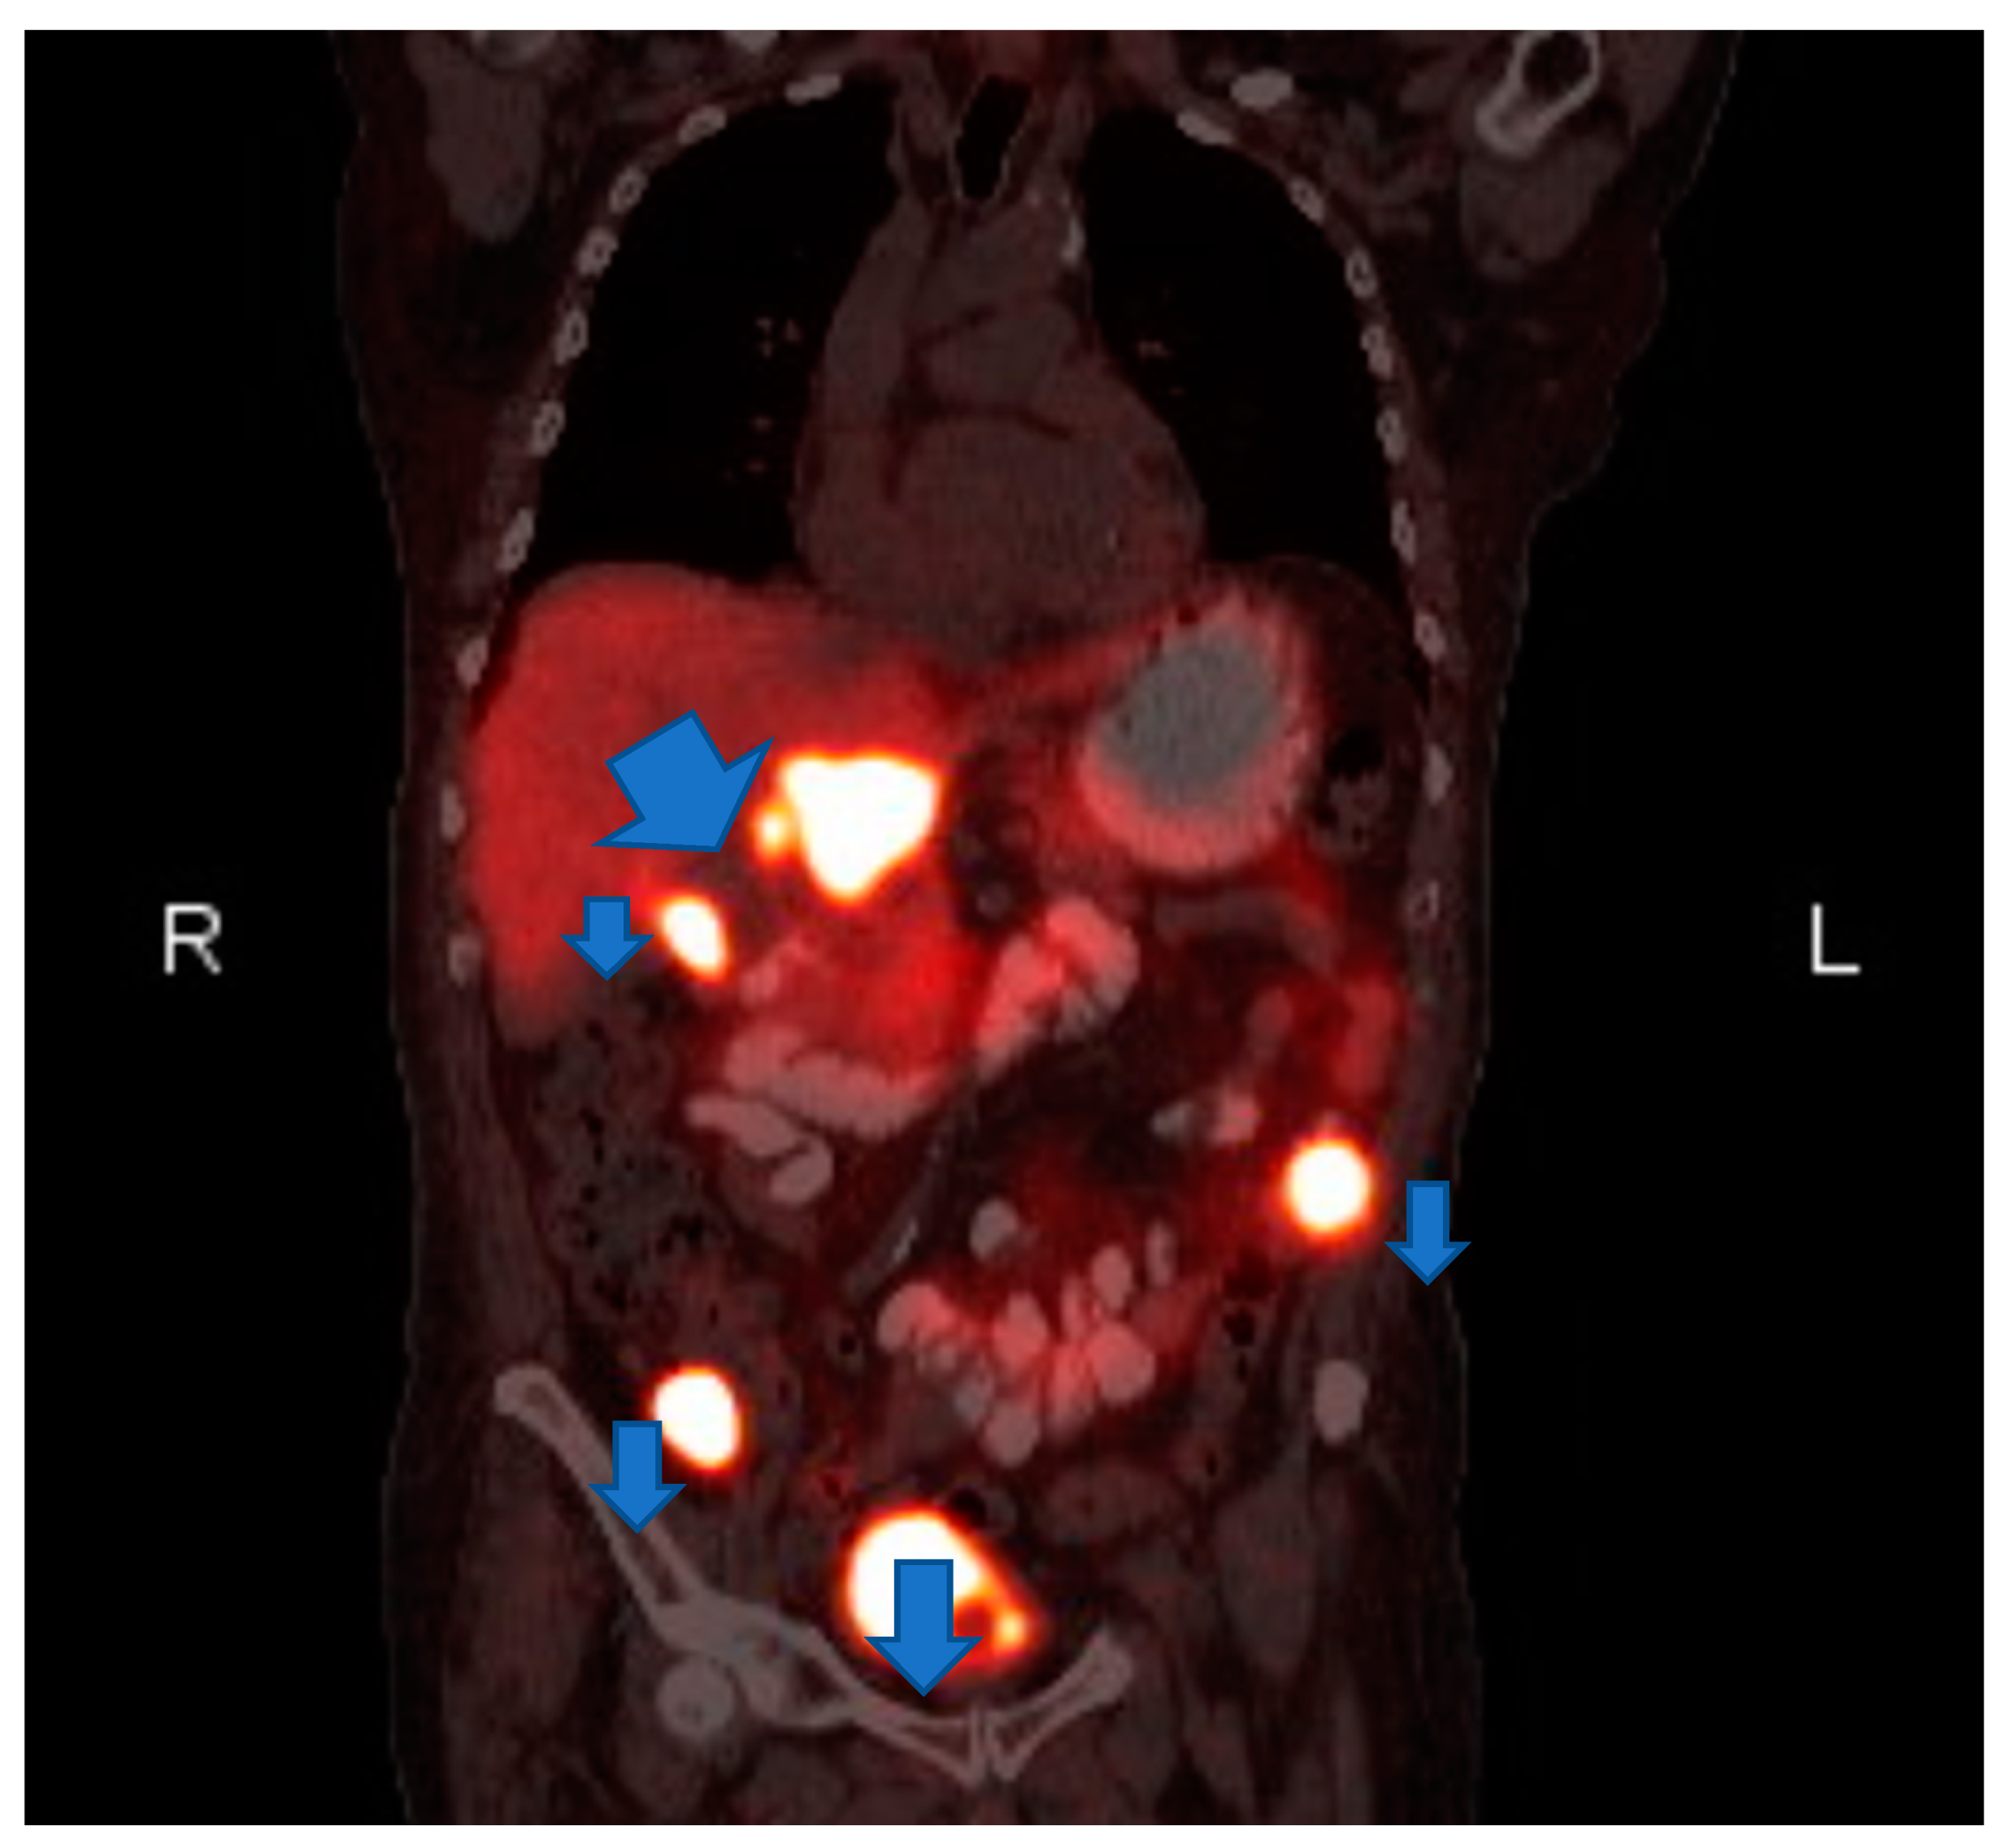

Laboratory testing revealed anemia (hemoglobin 9.2 g/dl) and hyponatremia (sodium 131). His urine metanephrine was 556 mcg/24 h, normetanephrine was 22,624 mcg/24 h and creatinine was 2.56 mg/dl. His INR was 4.26 which was high. On imaging, there was an abdominal mass on the right upper kidney as well as an abdominal hematoma. Computer tomography (CT) of abdomen showed left lower abdominal wall hematoma and prominent multilobulated soft tissue mass within the right retroperitoneum superior to the right kidney in the region of right adrenal gland involving the liver, vena cava and kidney. Magnetic resonance imaging (MRI) of abdomen and pelvis showed postoperative changes after right adrenalectomy with 7.8 cm heterogenous multilocular enhancing mass in the surgical bed abutting the right posterior wall and close to the right kidney and Inferior vena cava (IVC). The mass and the enlarged regional lymph nodes together caused marked compression of the IVC. Heterogeneity and enhancing focus in the posterior right hepatic lobe indicated the invasion of the right adrenal gland. (Figure 1) Positron emission tomography (PET) gallium-68 DOTA-DPhe1, Tyr3-octreotate ((68Ga)Ga-DOTA-TATE) imaging showed liver and mesentery metastases. (Figure 2) He was diagnosed with right metastatic malignant adrenal lesion surrounding IVC along with the syndrome of inappropriate antidiuretic hormone (SIADH).

Figure 2. Coronal Postitron Emission Tomography/Computed Tomography (PET/CT). gallium-68 DOTA-DPhe1, Tyr3-octreotate (68Ga)Ga-DOTA-TATE Abnormal gallium dotatate accumulation in the right adrenalectomy bed, upper abdominal lymph nodes and two mesenteric nodules.